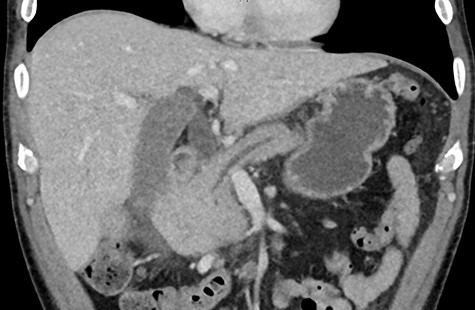

Biochemistry results revealed a lipase and bilirubin of 1105 units/L and 93 umol/L, respectively. Subsequently, a 12.5 × 11.3 cm heterogenous mass arising from the right kidney was found on a contrast enhanced computed tomography (CT) scan (Fig. 1). This mass was associated with a non-contiguous adrenal metastasis ipsilaterally and retrocaval lymphadenopathy adjacent to the pancreatic head resulting in biliary and pancreatic duct dilatation (Fig. 2). A staging CT chest with intravenous contrast was then performed revealing mediastinal lymphadenopathy suggestive of metastasis.